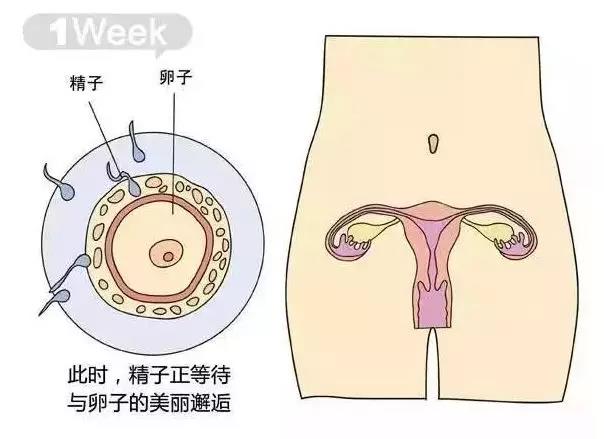

1周

受孕

万千的精子进入女性体内

剩下只有一个最强壮的精子游向

输卵管黏液膜褶内的一个女性卵子

当女性排卵的时候

1个卵子会被送进输卵管里

在接下来的12~24小时里

如果3亿5千万精子(平均一次射精的量)

中有1个成功到达输卵管并钻进卵子的外膜

就会使卵子受精